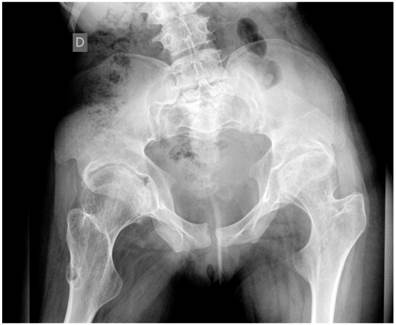

Group 3: To further delineate the joint pathology; Anteroposterior pelvis radiograph showed significant epiphyseal dysplasia associated with extensive fragmentation in a 19-year-old girl. This patient showed severe osteoarthritis (defined as the presence of hip pain and radiographic features of marked degenerative changes using Kellgren-Lawrence scoring system). The grade of osteoarthritis in these children was compatible with grade 3 of Kellgren-Lawrence score. Large osteophytes associated with marked narrowing of the joint spaces, sclerosis and subsequent deformity of the bony contour, coxa valga and osteopenia were present (fig 6).

Fig 6

Anteroposterior hip radiograph in a 19-year-old girl showed severe osteoarthritis matching the grade III of Kellgren-Lawrence grading scale. Note the flattened and dysplastic epiphyses associated with large osteophytes with marked narrowing of the joint spaces, sclerosis and subsequent deformity of the bony contour, coxa valga and osteopenia.